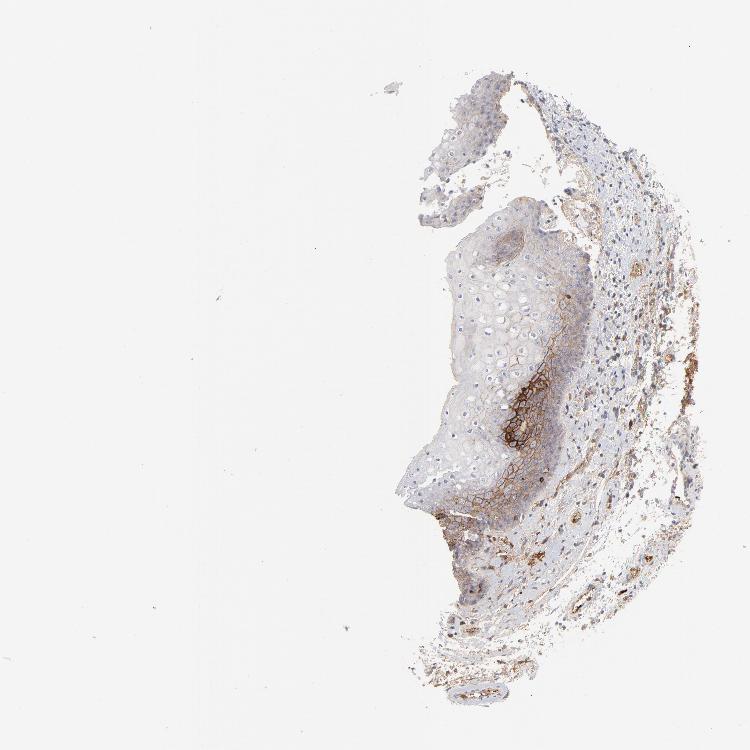

SKIN 1 - Antibody stainingi

Antibody staining in the annotated cell types in the current human tissue is reported as not detected, low, medium, or high, based on conventional immunohistochemistry profiling in selected tissues. This score is based on the combination of the staining intensity and fraction of stained cells.

Each image is clickable and will lead to virtual microscopy that enables deeper exploration of all samples and also displays staining intensity scores, fraction scores and subcellular localization as well as patient and tissue information for each sample.

Antibody CAB003795

Langerhans Medium

Fibroblasts Low

Keratinocytes Medium

Melanocytes Not detected